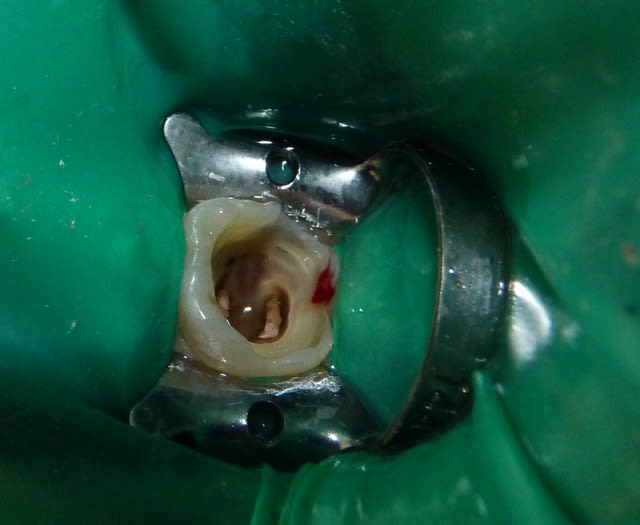

Qui ferait quoi dans le cas ci-dessous : 11 ans, patient en classe I, normodivergent, hygiène médiocre, très coopérant au fauteuil. 36 présente une carie similaire en lingual. Ces deux dents sont vitales.

Idéalement, je ferai un coiffage ou une pulpo au MTA, un moignon en compo ou CVI et une CPP (il fera une couronne à l'age adulte).

Pas possible financièrement (170 euros HN).

Donc soit je fais une séance galère sous digue avec coiffage au Dycal et restauration au composite pour SC17, soit j'extrais...